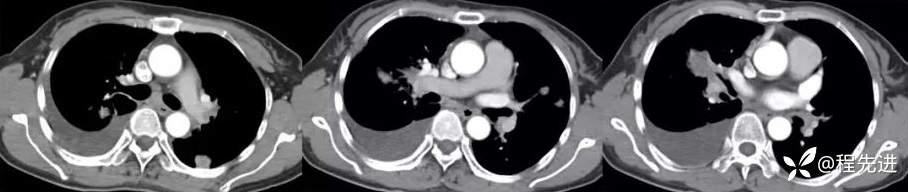

增强静脉期

肺窗冠状位重建